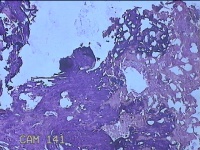

肛门肿物

性别

女

年龄

41岁

临床诊断

混合痔

一般病史

发现肛门肿物突出伴大便带血2年。

标本名称

大体所见

灰白暗红色皮肤肿物1.5x1.3x0.3cm一个,表面糜烂,切面灰白粉红色,质软。